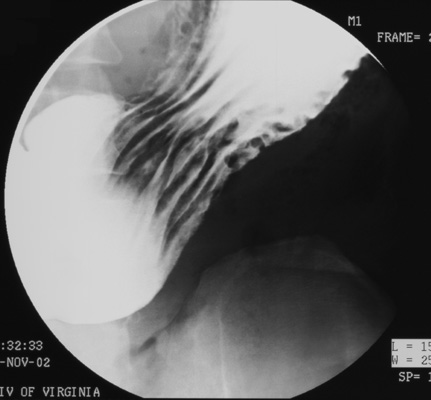

- Turn x-ray table upright. Use compression cone on fluoroscope to

obtain graded compression of duodenal bulb. Take two SCGC spots (Zoom to 6" or 9" FOV) of the bulb.